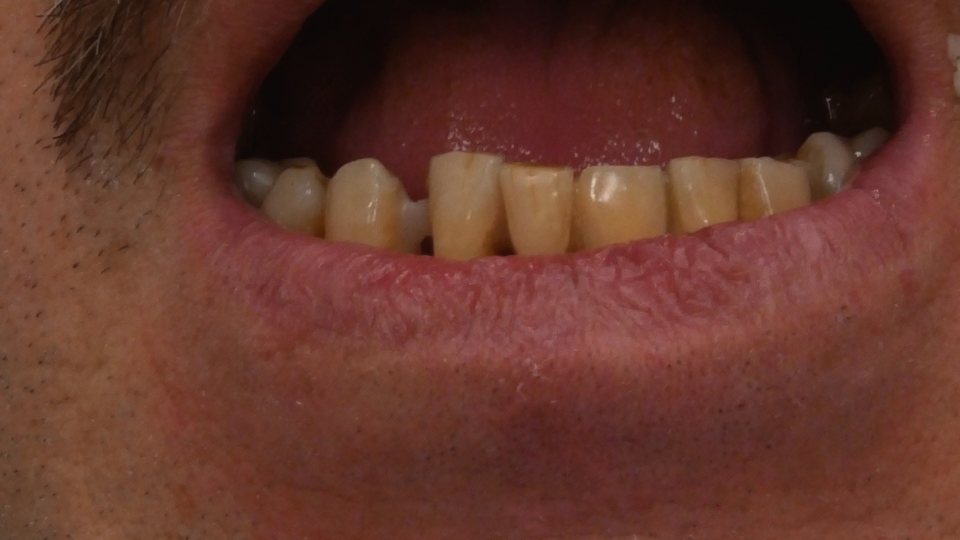

Jedną z popularniejszych metod stabilizacji zębów rozchwianych jest ich szynowanie. Metoda ta, wspierająca inne metody leczenia, jest powszechnie stosowana. Jednym z najnowocześniejszych materiałów wykorzystywanych w stomatologii do szynowania zębów jest taśma poliaramidowa. W opisanym przypadku autorzy pracy przedstawiają sposób uproszczenia całej procedury i ograniczenia ryzyka popełnienia błędu, szczególnie w sytuacji całkowitej utraty zęba. Uzyskano to dzięki zastosowaniu indeksu wykonanego z przezroczystego silikonu.

One of the more popular methods of stabilising loose teeth is to splint them. This method, aiding other methods of treatment, is generally used. One of the most modern materials used in dentistry for splinting teeth, is polyamide tape. In the case described the authors show how to simplify the whole procedure and limit the risk of making a mistake, particularly in the situation of total loss of one tooth. This was achieved thanks to the use of an index made out of transparent silicone.